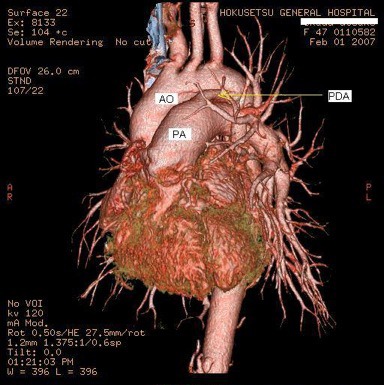

この症例は幼児期に何度も大学病院での根治手術が検討された。心臓カテーテル検査で、ファロー四徴症と動脈管開存症の合併と診断。この動脈管を通じて肺血流が十分に確保されているとの判断で内科的に経過観察してきた。カテーテル検査による診断は、最近の精細な心臓超音波検査やCT検査にて確認された。

図4: 造影CT検査、大動脈騎乗がよく分かる。

図5: 造影CT検査、右室流出路狭窄による肺動脈狭窄を認める。肺動脈弁は正常のようにみえる。

図6: 造影CT検査、画像を連続して分析すると、動脈管が大きく拡大し大動脈―肺動脈への血流を認める。

図7: 造影CT検査、3D画像を構成すると、大動脈と肺動脈の間に拡張した動脈管をみることができる。